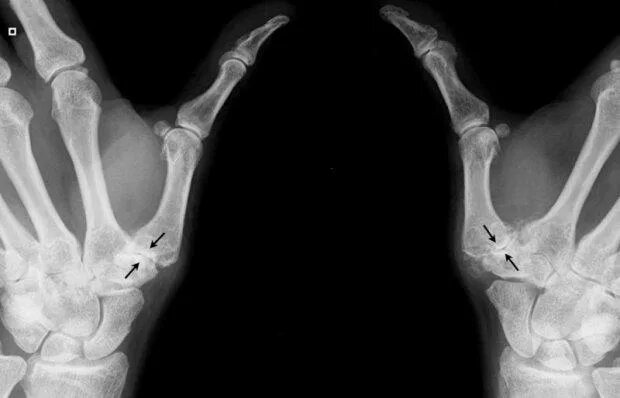

Артроз запястно пястного сустава